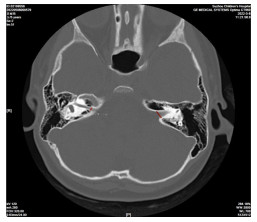

术前颞骨HRCT联合内耳MR在人工耳蜗植入患儿中的应用

武林, 贾慧惠, 陈萌萌, 顾维, 王爱平

2026, 24(1): 113-116. doi: 10.16766/j.cnki.issn.1674-4152.004342

67 2

摘要:

目的  针对重度感音神经性耳聋患儿人工耳蜗植入术(CI)中解剖结构复杂、电极植入风险高的临床难点,探讨术前颞骨高分辨率CT(HRCT)与内耳MRI多模态影像联合评估的应用价值,为优化手术方案、降低并发症风险提供影像学依据。  方法  选取苏州大学附属儿童医院2021年1月—2024年12月行CI治疗的重度或极重度感音神经性耳聋患儿192例(215患耳),对患儿行颞骨HRCT、内耳MR检查。比较2种方法对内耳畸形的诊断效能,以及电极植入异常情况;采用单因素和logistic回归分析研究电极植入异常的危险因素。  结果  192例(215耳)患儿中内耳发育畸形共140例(159耳),部分单侧畸形耳合并多种畸形;内耳MRI检查耳蜗畸形检出率低于颞骨HRCT(P<0.05)。经颞骨HRCT联合内耳MRI检查,有29耳电极植入异常,其中不伴内耳畸形植入异常率为5.36%(3/56),低于伴内耳畸形的16.35%(26/159,P<0.05)。Logistic多因素回归分析结果显示,前庭导水管宽度较高、面神经管迷路段缺失率较高、内淋巴囊扩大程度较高、术中脑脊液压力水平较高、患儿年龄较大是电极植入异常的独立危险因素(P<0.05)。  结论  术前颞骨HRCT联合内耳MRI可客观显示患儿内耳发育情况及解剖结构,且前庭导水管宽度、面神经管迷路段完整性、内淋巴囊扩大程度、术中脑脊液压力是电极植入异常的独立影响因素。